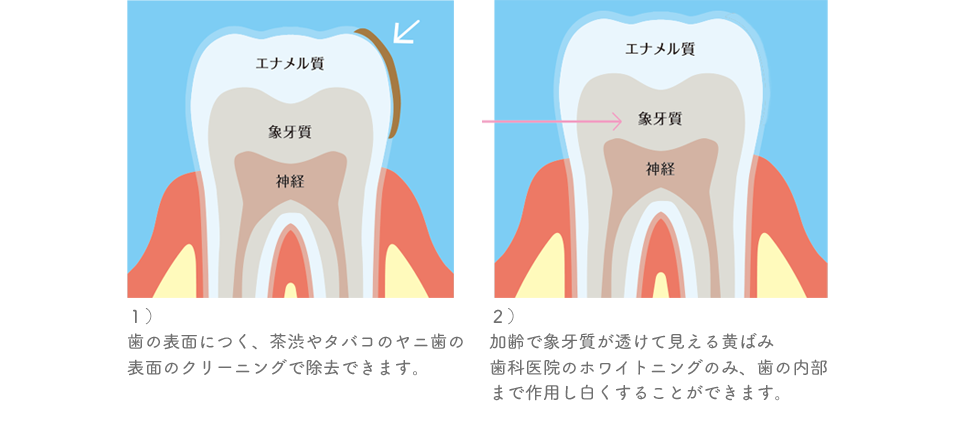

1)歯の表面の着色(飲食物・ヤニによる着色)

2)歯の内部の黄ばみ(象牙質の色が透けている)

の2種類があります。

1)の着色は、コーヒー・紅茶など茶渋やタバコのヤニが原因です。

2)の歯の内部の黄ばみは、加齢によって象牙質の厚みが増えるために、黄ばみが濃くなってきます。

若い時に比べて、「最近歯が黄ばんできたな・・?」と感じるのは、象牙質の厚みが増えたからなのです。

また、生まれつき象牙質が分厚く、黄ばみが濃い方もいらっしゃいます。

1)の飲食物・ヤニによる着色は、歯の表面をクリーニングすることで、きれいに除去することができます。

しかし、2)の歯の内部の黄ばみは、歯のクリーニングでは白くすることができません。

歯科医院のホワイトニングでのみ歯を白くすることができます。